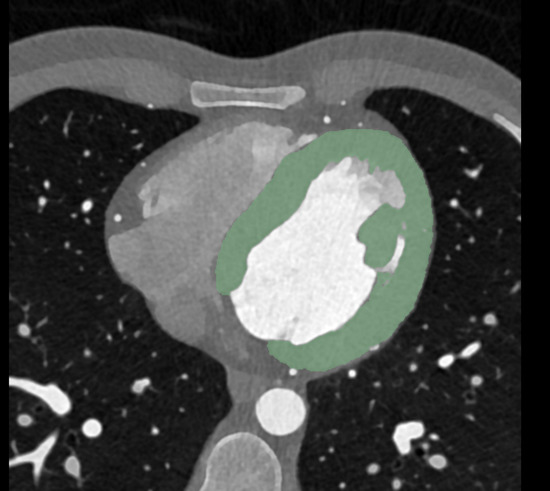

2.4. Chest CT Imaging Analysis

2.5. Radiomics Feature Extraction and Statistical Analysis